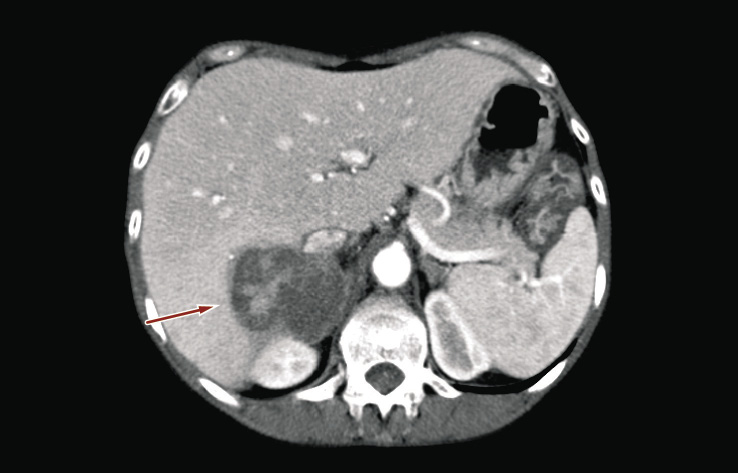

A 55-year-old woman was admitted to our Urology Unit on January 2014 to undergo a biopsy of right adrenal mass. Clinically, the patient suffered from continuous pain in the right lumbar region, a significant weight loss in the past two months (about 15 kg), and severe asthenia. Before hospitalization, ultrasonography showed a nonspecific mass located around the upper pole of the right kidney and abdominal computed tomography revealed a right adrenal neoplasm measuring 45 × 29 mm in diameter and bulging out toward the liver (Figures 1 and 2).

Figure 2. Abdominal computed tomography revealing the same adrenal mass (red arrow) in trasversal plan (one month before hospital admission)